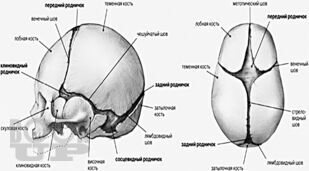

В учебном пособии представлены современные взгляды на вопросы этиологии, патогенеза, диагностики и оперативного лечения черепно-мозговой травмы у детей.